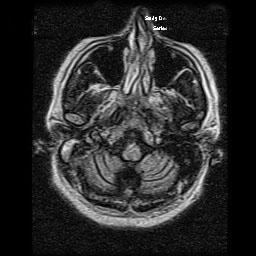

Novel missense variant in SPTBN2 possibly associated with spinocerebellar ataxia type 5 presenting as Parkinson´s disease

Spinocerebellar ataxias are a heterogeneous group of neurodegenerative diseases. There are more than 40 subtypes described so far, being spinocerebellar ataxia type 5 (SCA5) a rare autosomal-dominant ataxia with pure cerebellum involvement.  The gene responsible is the non-erythrocyte beta 2 spectrin gene (SPTBN2), encoding β-III spectrin, highly expressed in Purkinje cells. Onset is usually before 30 years, although it ranges from infancy to 70 years. The main clinical manifestations are limb and gait ataxia (> 90%); however, some patients also show trunk ataxia, sensory deficits, abnormal eye movements, dysarthria, and hyperactive deep tendon reflexes (25–90%).